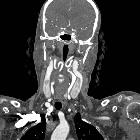

Kissing

carotids: a lovely term for an anatomic variant with great clinical significance. Coronal reconstructed image showing the two internal carotid arteries in close proximity (arrowheads).